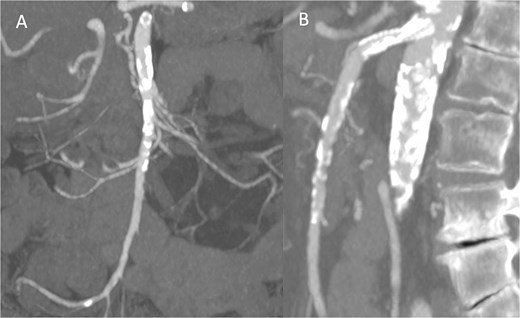

Pre-discharge follow-up CTA showing patent SMA and no complications, with coronal (A) and sagittal (B) images.